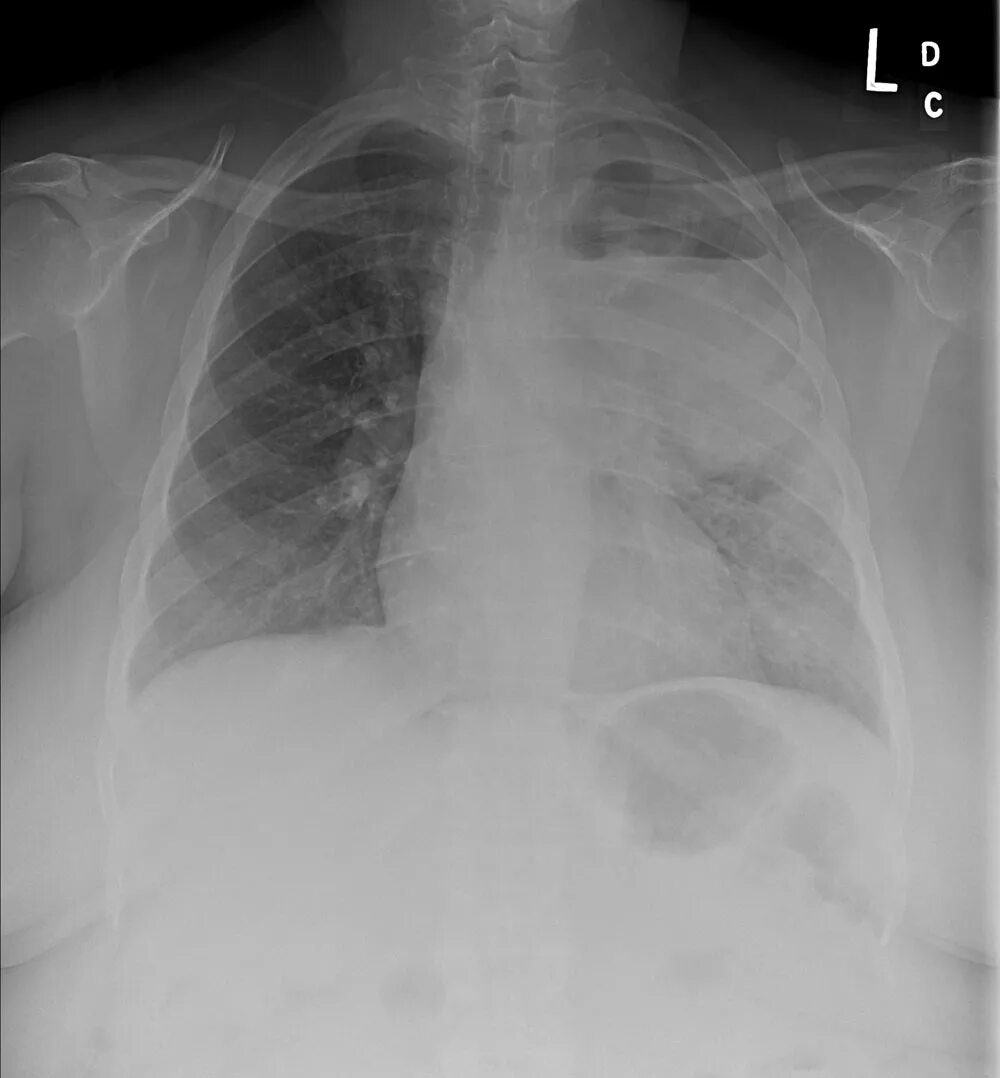

Метастазы в легких терапия